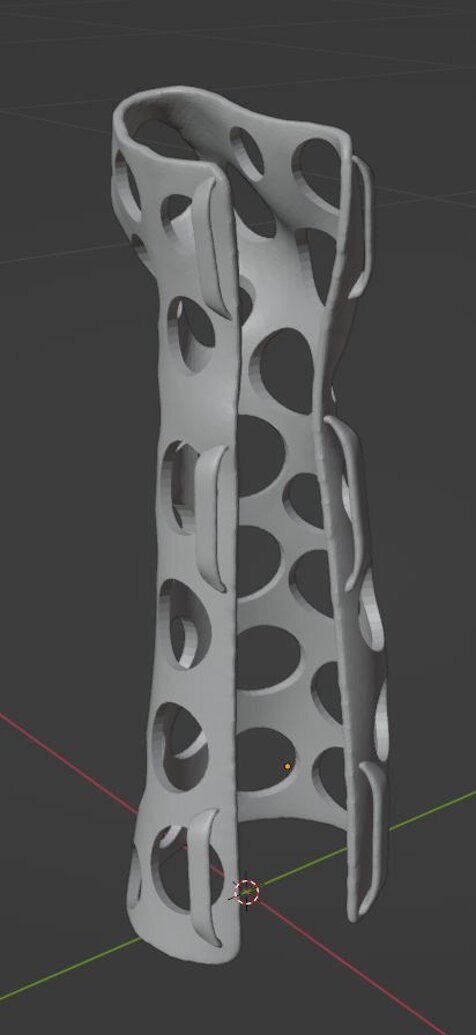

Lavoriamo nella distribuzione di dispositivi medici innovativi per la diagnostica del linfonodo sentinella e per la diagnostica epatologica grazie alla nostra avanzata innovazione nella tecnologia di elastografia epatica, . Offriamo soluzioni personalizzate per ortopedia sia come tutori che come CAST alternativi al gesso da frattura

Soluzioni Innovative per Diagnostica e Lifetech Immobilizzazione Fratture